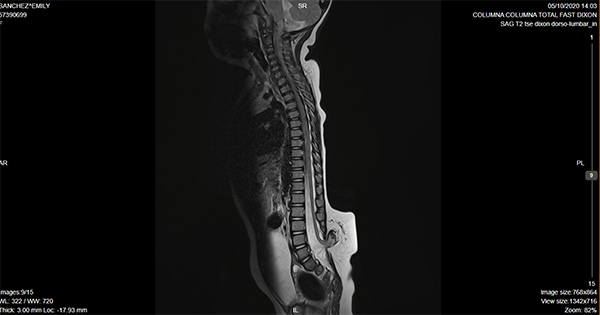

Caso ilustrativo n°3: Houkin tipo 3(Figura 3)

Paciente de 21 meses de vida, con diagnóstico de lipomielomeningocele lumbosacro, pie equinovaro bilateral. Urodinamia alterada con globo vesical asociado a pérdida de orina, cateterismo intermitente 3 veces/día. Potenciales evocados de miembros inferiores con alteración de la vía somestésica. Se realizó cirugía de desanclaje medular. Paciente permaneció en decúbito ventral 12 días con peso en herida. Posteriormente presentó colección de LCR en colgajo a los 7 días. La cual no fistulizó ni requirió punciones. Se manejó con tratamiento conservador y evolucionó favorablemente. Alta a los 14 días de la cirugía.

Se consideró Houkin tipo 3 por ser esperable, ya que la colección de LCR en este tipo de cirugías es muy frecuente, más allá del cierre hermético de la duramadre.

Figura 3: Imagen por Resonancia Magnética de columna lumbosacra donde se evidencia disrafismo lumbar, compatible con lipomielomeningocele.